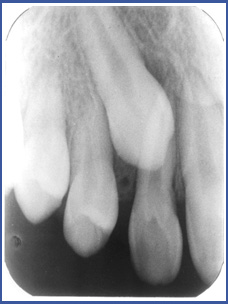

3. Неправильная траектория прорезывания. Постоянный зуб начинает развиваться в глубине десен и со временем прорезается. Зубы, у которых длинная траектория прорезывания, могут «ошибиться» и в результате останутся «запертыми» в деснах, в неправильном месте. Такие ситуации характерны для верхних клыков, у которых очень длинная траектория прорезывания (другие зубы тоже могут оказаться «запертыми», но реже). Частота появления «запертых» клыков у населения составляет 1%-3%

3.Если зуб «заперт» вследствие того, что траектория прорезывания неправильная, нужно обнажить «запертый» зуб хирургическим путем. Иногда простое обнажение зуба может изменить траекторию прорезывания, а иногда во время обнажения нужно приклеивать ортодонтическое приспособление на «запертый зуб» и активно вытягивать его на зубную дугу.

Шансы на удачное завершение лечения:

Лечение основывается на предположении, что «запертый» зуб не потерял свой потенциал прорезывания. Шансы достигнуть успеха в лечении «запертых» зубов очень велики в молодом возрасте (а в возрасте 40 лет составляют около 50%). Причина в том, что со временем зуб прирастает к кости в десне, а в таком случае теряется потенциал прорезывания зуба. Поэтому лучше прорезывать «запертые» зубы в более молодом возрасте.